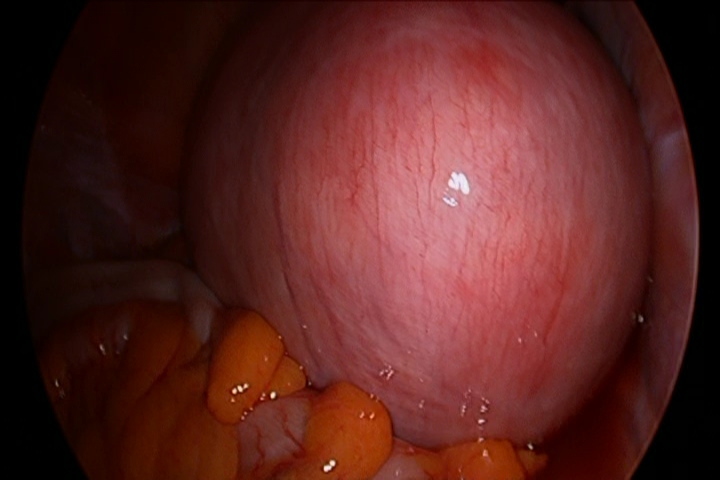

자궁선근증은 비정상적으로 존재하는 자궁내막 조직에 의해서 자궁의 크기가 커지는 질환으로, 자궁벽이 점차 두꺼워지는 특징을 보입니다.

대표적인 증상으로 빈혈을 동반하는 생리 과다와 생리통을 들 수 있습니다. 또한 장기간 지속되는 골반통도 주요한 증상 중 하나입니다.

한번 발생하면 폐경 전까지 계속 커지고 악화될수 있어 조기 발견이 중요하며, 가임기 여성의경우에는 가급적 빨리 임신, 출산을 하는것이 좋습니다.